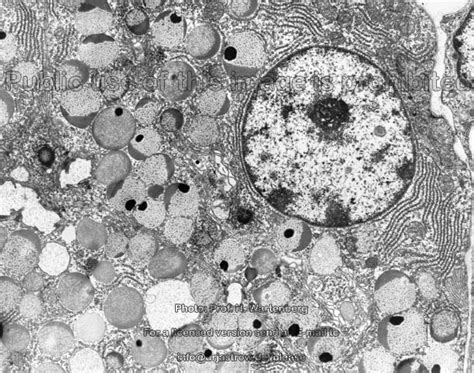

salivary glands Dr.Jastrow's electron microscopic atlas

parotid gland anatomy